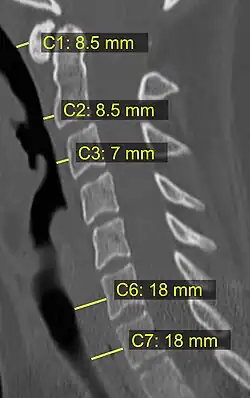

In trauma, an increased thickness of the prevertebral space is a sign of injury, and can be measured with medical imaging.[4]

On plain radiography, prevertebral space should be less than 6 mm at C3 vertebral level in children; while in adults, the space should be less than 6 mm at C2 level and less than 22 mm at C6 level. Causes of enlarged prevertebral space could be edema, hematoma, abscess, tumors, and post surgical changes.[5]